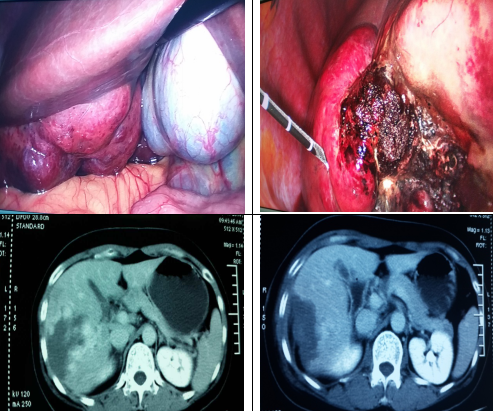

组图2 左上图片为术中所见肝血管瘤表现,肿瘤突出肝表面,可压迫周围脏器,2图为微波消融术后肿瘤改变,血管瘤组织微波后坏死,下两图为同一患者手术前后CT对比,箭头处示原肝脏血管瘤病变消融前后CT影像改变,对比可见术后区域原血管瘤病灶清除,周围正常肝脏组织保留良好,手术效果确切。